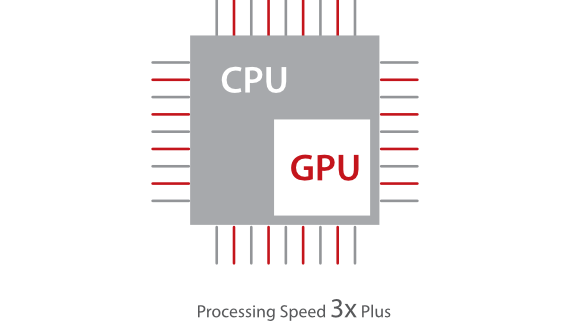

Mindray stellt mit seinen bahnbrechenden Ultraschallsystemen unter Beweis, worauf es im klinischen Alltag ankommt. Wir entwickeln kontinuierlich innovative Ultraschalltechnologien. Das DC-60 ECHO mit X-Insight ist ein exzellenter Beweis daf├╝r, wie unsere Ger?te h?chsten Anspr├╝chen gerecht werden und die moderne Medizintechnik noch besser und effizienter machen. Voller Vertrauen blicken wir mit X-Insight in die Zukunft. Das DC-60 Expert ├╝berzeugt als extrem leistungsf?hige Ultraschalll?sung. Mit diesem System leistet Mindray einen weiteren Beitrag dazu, in der Ultraschallbildgebung neue Ma?st?be zu setzen.